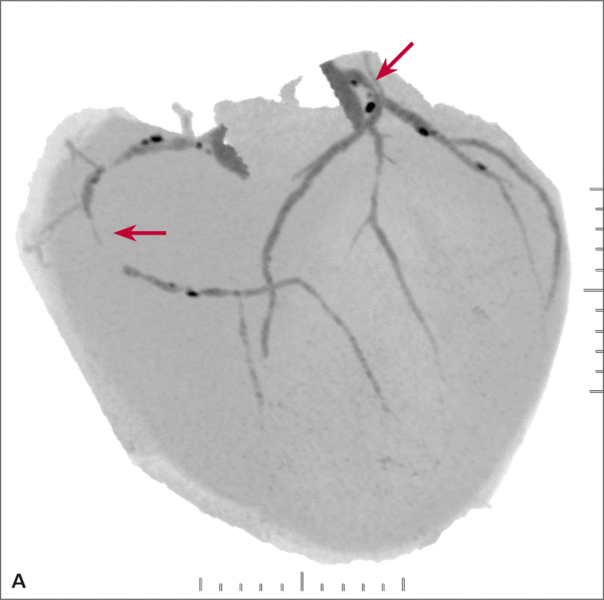

Mężczyzna, lat 68, z niecharakterystycznymi bólami w klatce piersiowej zgłosił się do specjalistycznej przychodni kardiologicznej. W wywiadzie rodzinnym podawał chorobę wieńcową w rodzinie, a osobniczym – nadciśnienie tętnicze i zwiększone stężenie cholesterolu. Wykonana próba wysiłkowa była niediagnostyczna (4,6 MET). Badanie echokardiograficzne nie wykazało istotnych nieprawidłowości. Badanie TK wykonane w trybie ambulatoryjnym uwidoczniło wielopoziomowe zmiany w prawej i lewej tętnicy wieńcowej (ryc. 1A), 50% zwężenie pnia lewej tętnicy wieńcowej z blaszką małej gęstości z remodelingiem dodatnim ściany naczynia (ryc. 1B) oraz niedrożność prawej tętnicy wieńcowej w segmencie 2/3 i wielopoziomowe zmiany w gałęzi diagonalnej i okalającej (ryc. 1C).

RYCINA 1. [A] Rekonstrukcja MIP Inversion. Niedrożność prawej tętnicy wieńcowej. [B] Rekonstrukcja MPR 2D – widoczne światło pnia lewej tętnicy wieńcowej (czerwona strzałka) oraz blaszka o niskiej gęstości powodująca bardzo dużego stopnia remodeling dodatni ściany naczynia (strzałka biała). [C] Rekonstrukcja MPR po krzywej wzdłuż osi długiej prawej tętnicy wieńcowej – wielopoziomowe zmiany niskiej gęstości z niedrożnością segmentu 2.